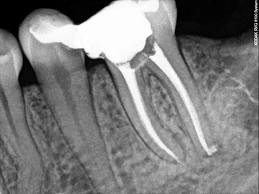

| El avance en el desarrollo

tecnológico de la aleación niquel-titanio, ha

hecho efectiva la utilización del instrumental rotatorio

en endodoncia durante la etapa biomecánica para

conformar el conducto para la limpieza y su posterior

obturación.